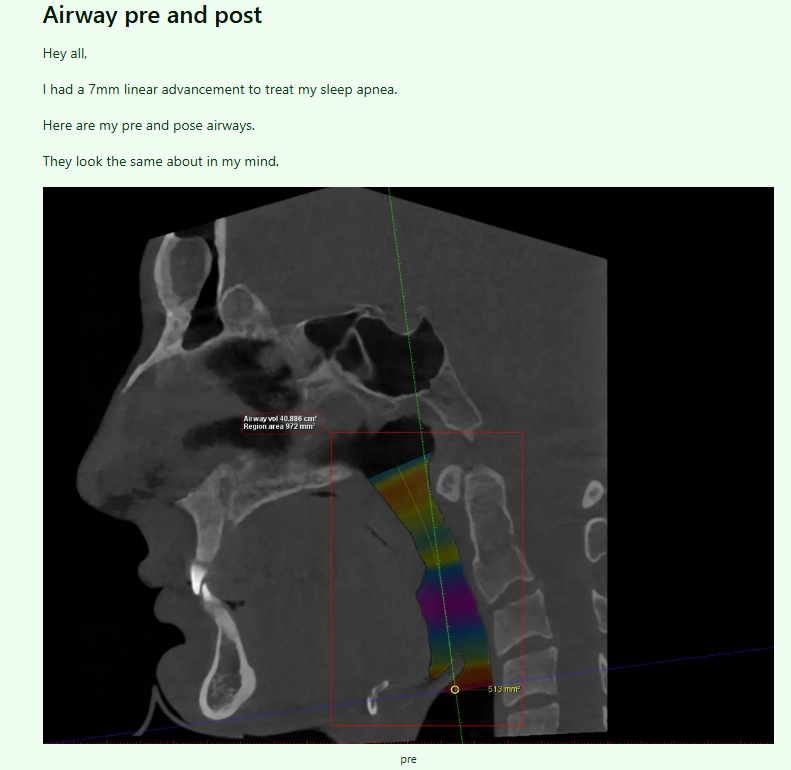

he/she had 7mm advancement on both jaws to cure their alleged "sleep apnea"

airway turns out to be the same after the surgery.

How did this individual have sleep apnea in the first place while having 1.5x the size of an average airway and 2-2.5x airway size of most people struggling with sleep apnea